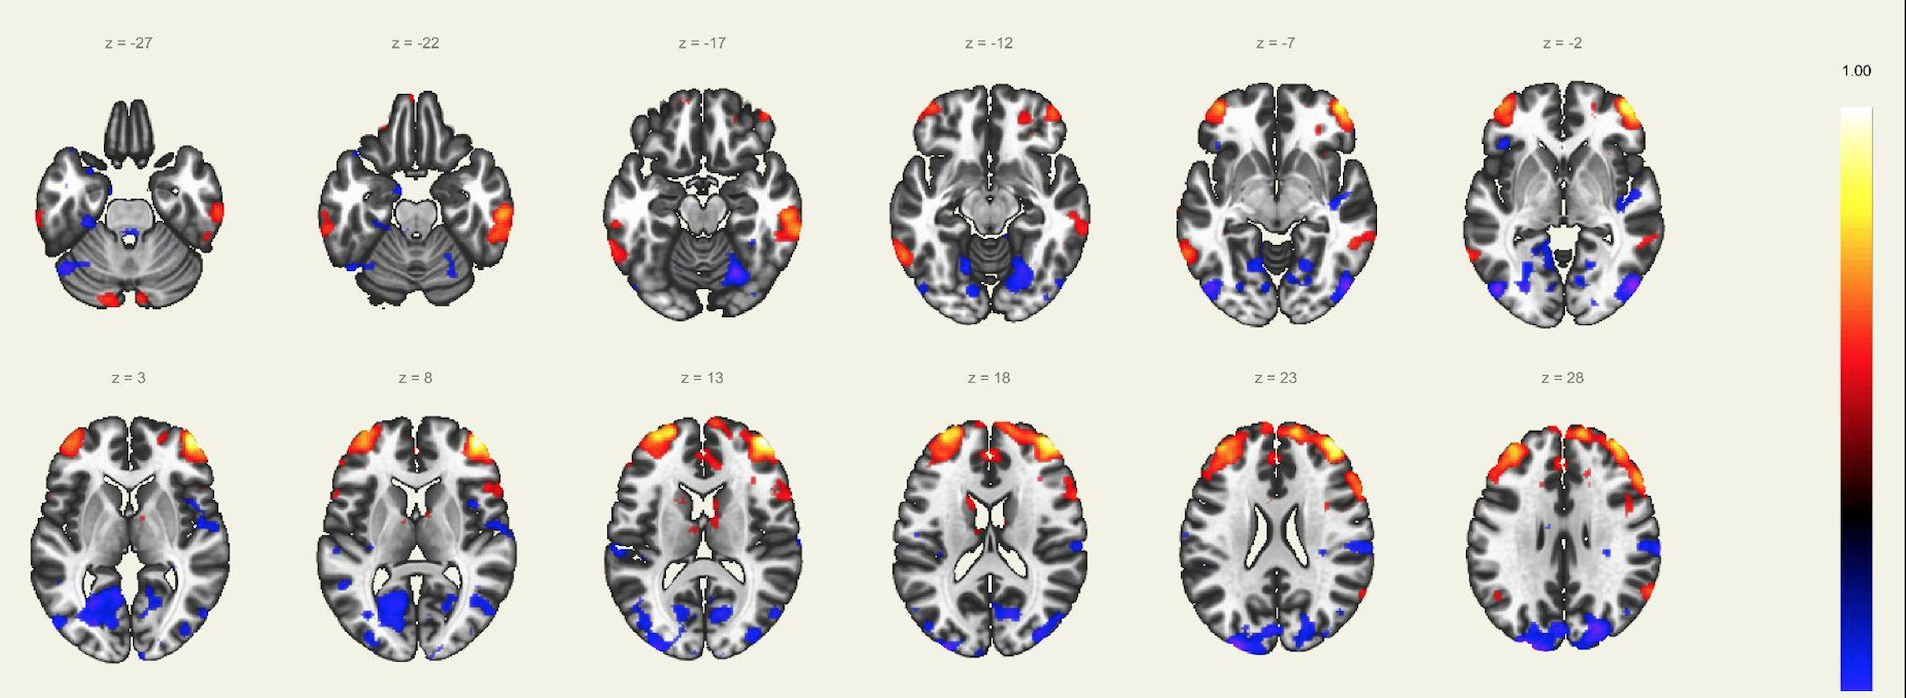

En este estudio, el escaneo se realizó con un resonador de 3 Tesla del servicio de diagnóstico por imágenes de la Clínica Internacional, a un paciente joven, sin comorbilidades ni antecedentes de importancia, el cual estuvo despierto en todo momento y con los ojos cerrados. Además, se le dio instrucciones de completar palabras mentalmente sin emitir sonido alguno o hacer gestos, llegando a identificarse las distintas redes cerebrales detalladas posteriormente.

El estudio fue realizado con secuencia BOLD, con los siguientes parámetros: cortes: 40, factor de distancia: 0%, Field of View: 240 mm, grosor de corte: 4 mm, tamaño de vóxel: 3.8 x 3.8 x 4 mm, TR: 3000 ms, TE: 30 ms, Umbral: 4 y tamaño del paradigma 20.

A pesar de la ausencia actividad física, resulta imposible indicar que no se esté realizando ningún tipo de actividad mental, como recuerdos o el uso de la imaginación. La consecuencia de esto se ve reflejada en los cambios de la actividad neuronal.16 A través de este método de vóxel semilla se ha logrado identificar distintas redes de conectividad funcional descritos a continuación:

Red de Atención Dorsal:

Constituida por la corteza cingular anterior, ambas ínsulas y el área motora suplementaria, la cual juega un rol importante en la regulación de los cambios dinámicos en las otras redes, por lo que su disfunción afecta directamente en el correcto funcionamiento de las otras redes. Otra característica conocida, es la necesidad de operatividad de esta área para la realización de rápidos cambios de comportamiento. Evidentemente, el inicio del control de los procesos de cognición se ve determinado por el correcto funcionamiento de esta red sobresaliente.

Esta red la constituyen los ganglios basales, sustancia negra, núcleo subtalámico, núcleo estriado y el globo pálido. Estas estructuras localizadas en la región basal del cerebro están involucradas en muchas funciones como la modulación de las áreas motoras, cognición y emociones. Consecuentemente, forman parte del aprendizaje de comportamientos complejos y difíciles, debido a la gran coordinación durante la realización de movimiento involucrado estas actividades.

Red del Lenguaje:

Implica las regiones prefrontales, temporo-parietal y subcortical, además de las ya conocidas áreas de Broca y Wernicke. El habla, el entendimiento, lectura, interpretación, mímicas; son algunas de las funciones más importantes de esta red. Adicionalmente, el área de Broca es asiento de las neuronas espejo, las cuales intervienen en el entendimiento e imitación de actividades motoras.